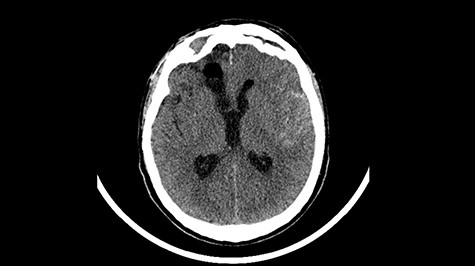

A 49-year-old patient presented after surgical treatment of nasal polyps, with headache and consciousness disorders (behavioral changes, drowsiness and allophenic orientation disorders). Computed tomography (CT) scan showed (Fig. 1) a presence of blood in fluid spaces, widening of the ventricular system (without active hydrocephalus features) and presence of air in the frontal horns of the lateral ventricles and features of cerebral edema. Due to the subarachnoid hemorrhage, an angio-CT and CT scan was performed, showing no vascular malformation. The patient's condition deteriorated with a drop in Glasgow Coma Scale (GCS) to 9, strongly expressed meningeal syndrome and a fever of > 38°C. In the performed cerebrospinal fluid examination a typical picture for bacterial infection, cultures negative. Treatment was implemented in accordance with the neuro-infections algorithm. Clinical and laboratory features of neuroinfections have withdrawn. The neurological condition of the patient improved to GCS 11. Control head CT (Fig. 2) showed enlargement of the ventricular system with cerebrospinal fluid transudation.

Head CT after polypectomy—presence of blood in fluid spaces, widening of the ventricular system, presence of air in the frontal horns of the lateral ventricles, features of cerebral edema. (Department of Neurosurgery Neurotraumatology and Pediatric Surgery own material).

In described case, a head CT scan after polypectomy confirmed the subarachnoid hemorrhage (Fig. 1). In addition, the presence of air in the ventricular system was visible, and presence of defects of the upper left orbital wall and ethmoid on both sides (Fig. 3). In the CT scan sphenoid sinus, frontal and ethmoidal sinuses on both sides and right maxillary sinus airless, filled with blood and soft tissue. The changes also concerned the lateral part of the left maxillary sinus (Fig. 4).